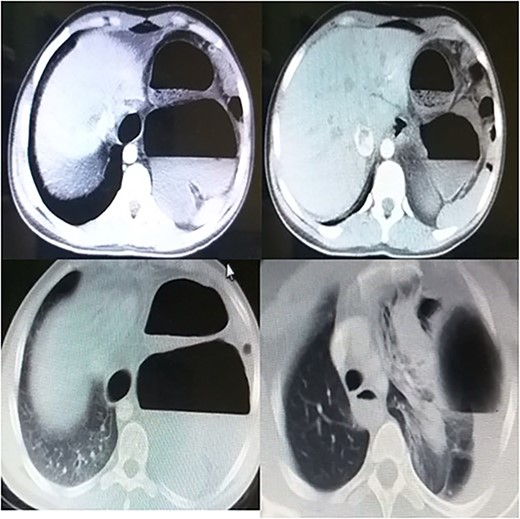

Laboratory tests showed white blood cells count of 9000/microliter with neutrophils 82%, mild anemia (Hb = 10 g/dl) and respiratory alkalosis (pH = 7.46, pCO2 = 28, and HCO3 = 20). Chest x-ray (CXR) of the chest was not able to visualize the left hemidiaphragm with a hollow viscus in the left thoracic cavity and a right shift of the mediastinum (Fig. 1). Computed tomography (CT) scan showed several viscera in the left thoracic cavity, containing air-fluid levels with the fluid not being homogeneous, pushing the left lung, the heart and the mediastinum to the right (Fig. 2). The CT also showed dilation of the esophagus with a presence of a fluid-gas level (Fig. 2). Additionally, there was atelectasis in the left lung. Finally, the liver and pancreas were in their normal position. An endoscopy was performed, which visualized the DH, which was 3 cm.

The surgical procedure was performed under general anesthesia with double-lumen tube and high airway pressure with low ventilation. Left lung was isolated, and a left lateral thoracotomy through the seventh intercostal space was performed. The spleen, stomach, omentum and part of the colon were found in the left chest, as shown in Fig. 3.

The diaphragm, which was found torn in its muscular section, was reached, and the abdominal viscera was returned to the abdomen. The diaphragm was then repaired, and the left lung was well disseminated (Fig. 4).